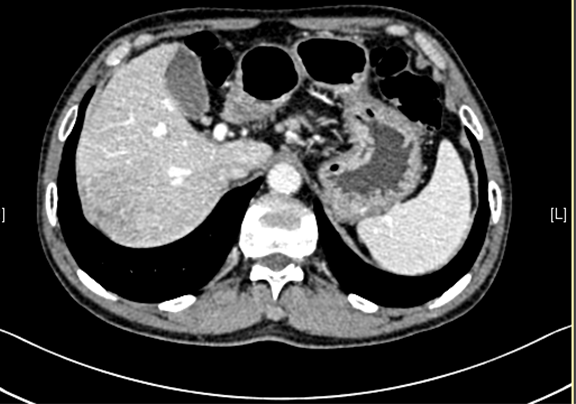

下腹部增强CT示:考虑肝右后叶肝Ca可能性大。肝顶异常强化灶,不除外不典型增生结节(DN)并癌变。肝硬化、脾大。

术前CT检查:

静脉期